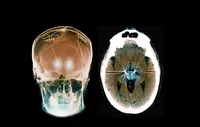

۹ روز زندگی با ریه‌ای بیگانه

نخستین ریه خوکی در بدن انسان نفس کشید

ریهٔ خوکی در بدن انسان به کار افتاد. جراحان چینی توانستند برای نخستین بار ریه اصلاح‌شده ژنتیکی یک خوک را به بدن انسانی با مرگ مغزی پیوند بزنند و به مدت ۹ روز شاهد عملکرد آن باشند. این موفقیت تاریخی، که بدون بروز «رد فوری» رخ داد، امید‌ها را به آینده پیوند اعضای حیوانی در انسان و یافتن پاسخی برای بحران جهانی کمبود اعضا زنده کرده است.

در یک دستاورد علمی که می‌تواند سرآغاز عصری تازه در درمان بیماری‌های لاعلاج باشد، گروهی از جراحان در چین برای نخستین بار موفق شدند «ریه اصلاح‌شده ژنتیکی خوک» (Genetically Modified Pig Lung) را به یک انسان پیوند بزنند. گیرنده این عضو، مردی ۳۹ ساله با وضعیت مرگ مغزی بود که پیش از این امیدی به بازگشت به زندگی نداشت. شگفتی این آزمایش آنجا بود که ریه خوکی به مدت نه روز کامل در بدن او به فعالیت ادامه داد؛ بدون آنکه علائم «رد فوری» (Hyperacute Rejection) واکنش ایمنی سریع و مرگبار بدن به عضو بیگانه دیده شود.

این رویداد که در مجله معتبر «نیچر مدیسین» (Nature Medicine) منتشر شده است، نقطه عطفی در پژوهش‌های «زاونترازپلانتیشن» (Xenotransplantation) یا همان پیوند اندام‌های حیوانی به انسان محسوب می‌شود. پژوهشی که می‌تواند در آینده نزدیک جان هزارانش بیمار در سراسر جهان را نجات دهد.